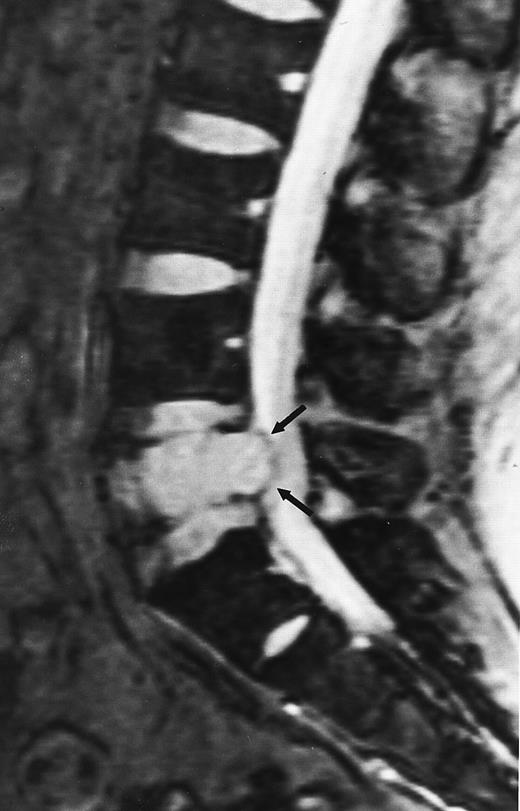

An 8-year-old boy with Burkitt's lymphoma and diffuse marrow involvement. Fat-suppressed, T2-weighted fast spin echo (3000/96, TR/TE) sagittal MR image of the lumbar spine shows heterogeneous signal intensity of the bone marrow and epidural extension of tumor (arrowheads) at the level of L5 and L2, with apparent preservation of the vertebral cortex.